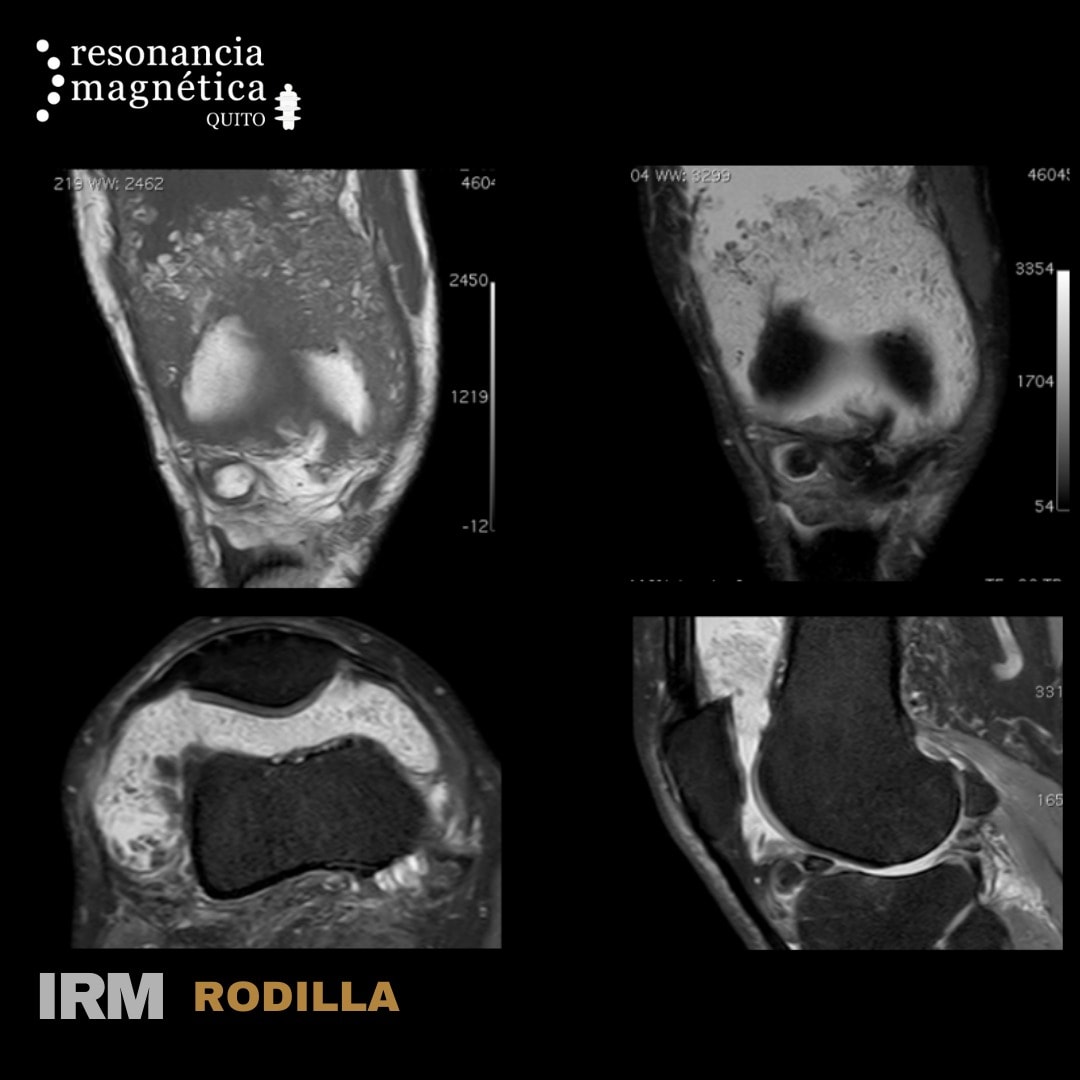

RM Rodilla

Paciente masculino de 69 años con dolor e hinchazón de la rodilla derecha de una semana de evolución episodios repetitivos desde hace 2 años. SINOVITIS VELLOSO NODULAR PIGMENTADA Localización: articulaciones (80% rodillas), bolsas serosas, varias tendínosis. Puede ser masa nodular focal o difusa con proliferación vellonodular de toda la sinovial. La RM es diagnóstico en el 95% focos de hemosiderina. Derrame articular.

Las patologías y lesiones detectadas mediante una RM de rodilla son muy variadas: rotura de menisco o de ligamento cruzado, tendinitis o lesiones en los tendones, enfermedades degenerativas como la artrosis. En ocasiones, permite observar la existencia de un derrame sinovial que está provocando dolor agudo en el paciente. En los casos de mayor gravedad, la resonancia de rodilla será el método de detección de tumores o metástasis óseas

Se puede identificar lo siguiente:

• Caracterización inicial, detección o exclusión de tumores óseos y de partes blandas

• Evaluación preoperatoria y planificación de cirugía de tumores de hueso y partes blandas.

• Detección y evaluación de complicaciones relacionadas con tumores óseos y de partes blandas.

• Lesiones óseas y musculares.

• Infecciones de hueso y partes blandas.

• Enfermedades congénitas y del crecimiento: displasia y variantes normales